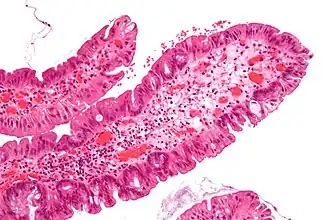

| Villous adenoma | 15%[16] to 40%[15] | Over 75% villous[14] | .jpg)

| |

The villous subdivision is associated with the highest malignant potential because they generally have the largest surface area. (This is because the villi are projections into the lumen and hence have a bigger surface area.) However, villous adenomas are no more likely than tubular or tubulovillous adenomas to become cancerous if their sizes are all the same.[18]

- Villous adenoma: 40% risk of cancer

Micrograph of a villous adenoma. These polyps are considered to have a high risk of malignant transformation. H&E stain.

Micrograph of a villous adenoma. These polyps are considered to have a high risk of malignant transformation. H&E stain. -